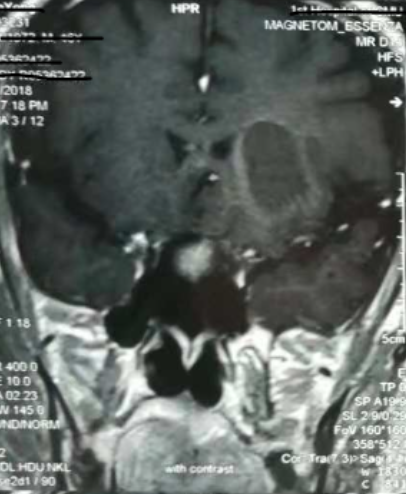

增強(qiáng)核磁提示:血腫液化周邊增強(qiáng)